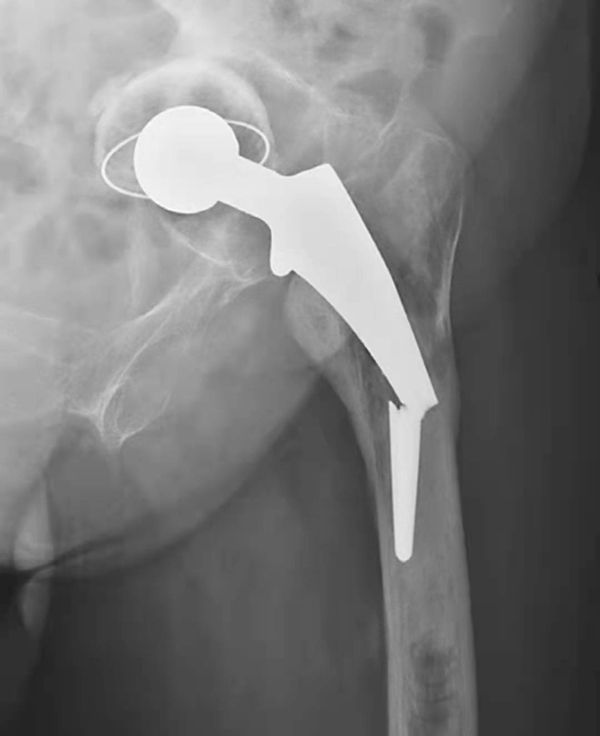

图1 人工髋关节置换术后正常X线表现

平片,示右侧股骨上段骨质疏松,人工股骨柄周围明显骨质吸收,透亮带明显增宽,髋臼杯位置未见改变